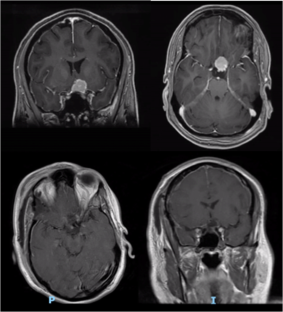

Fig. 1

The resection of tuberculum sellae meningiomas poses a challenge particularly when dealing with the medial aspect of the optic nerve. Dissection of the tumor off the optic nerve is usually carried out in the blind spot “behind” the optic nerve. We describe a contralateral approach for asymmetric tuberculum sellae meningiomas, allowing direct visualization of the medial optic nerve.

Contralateral lateral supraorbital approach was performed, and complete tumor resection was achieved without any injury to the optic nerve.

The contralateral approach for asymmetric tuberculum sellae meningioma is an efficient technique allowing improved visualization of the medial optic nerve.